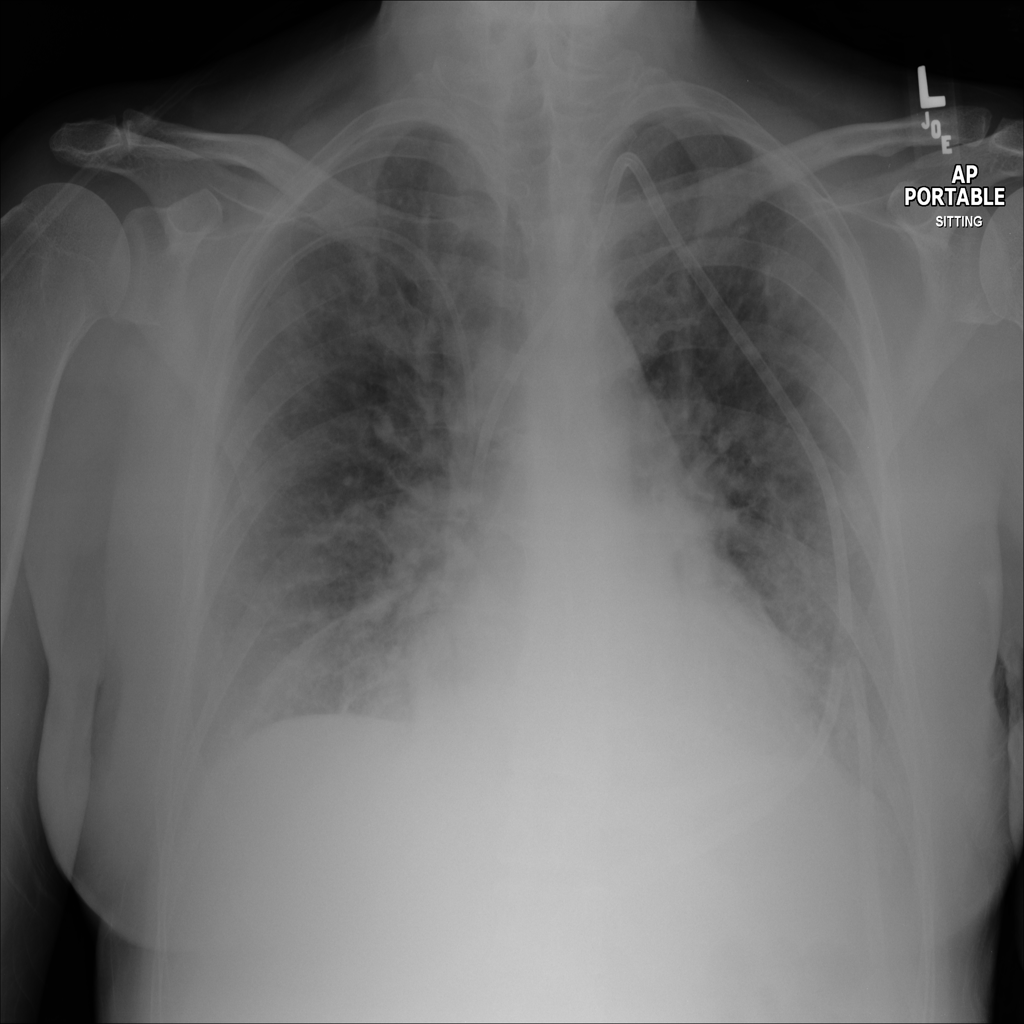

Showing up to 90 reference images for Edema.

PAT-E828 · IMG-004Edema

PAT-E828 · IMG-004

AP